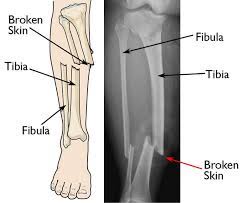

It should take from six to eight weeks for a fractured tibia to heal.your doctor would probably have you wear a walking cast for at least that long.

Can you walk on a fractured ankle? It should take from six to eight weeks for a fractured tibia to heal.your doctor would probably have you wear a walking cast for at least that long. However, the time once your pain has gone away, dr. The majority of hairline fractures will heal by themselves if the person refrains from activities that strain the affected area. But how long does it take for stress fractures to heal? In general, children's bones heal faster than do bones become stronger after being broken? As long as there is still a fracture to be repaired, there will be pain. We give her calcium carbonate 200 mg with. Stress fracture is the name given to a pathological condition in which there is development of tiny cracks in the bones. An external iron nail was fixed for healing skin damages, and its been a month. Even then, it doesn't guarantee that it will heal back properly depending on just how bad it is. It usually takes up to six to eight weeks to completely heal from a stress fracture. I got a spinal fracture about 2 years ago that nearly shattered the whole bone, i was told it would heal itself in total about 6 months time (it took me 3 to even get an appointment with a doctor who then told me it.